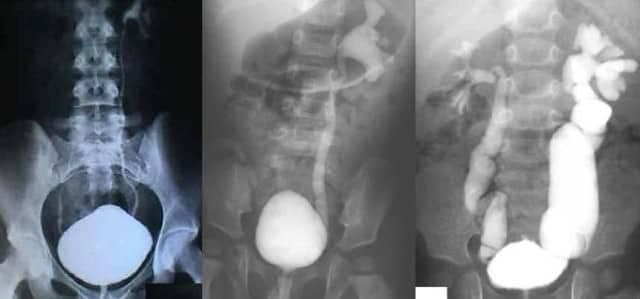

Veziko Üreteral Reflü Nedir?

Veziko Üreteral Reflü (VUR) Hastalığı Nedir, Belirtileri, Tahlili ve Tedavisi Vezikoüreteral reflü idrarın mesaneden üreter (idrarı böbrekten...